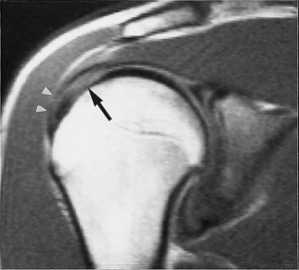

МРТ. Корональная Т2-зависимая томограмма с подавлением сигнала от жира. Полный разрыв сухожилия надостной мышцы.

МРТ плечевого сустава с подавлением сигнала от жира. Т2-взвешенная корональная МРТ. Перелом большого бугорка (стрелка).

При МРТ плечевого сустава косвенным признаком разрыва вращательной манжеты служит высокий сигнал на Т2-взвешенных от поверхности сустава до субакромиальной (субдельтовидной) сумки. Частичные разрывы чаще всего по передней поверхности сухожилия м.supraspinatus, реже примыкая к большой бугристости или сухожилия м. infraspinatus.

МРТ плечевого сустава. Т2-взвешенная корональная МРТ. Субакромиальное скопление жидкости - косвенный признак разрыва вращательной манжеты.

МРТ плечевого сустава. Т1-взвешенная корональная МРТ. Частичный разрыв вращательной манжеты.

МРТ плечевого сустава. Т2-взвешенная корональная МРТ. Передний разрыв вращательной манжеты